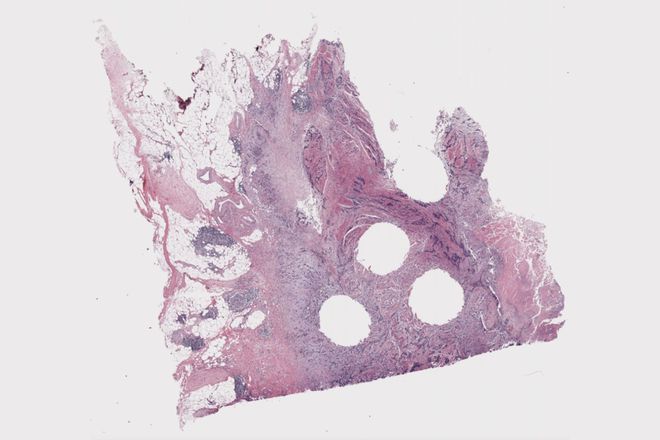

(来源:MITTechnologyReview)透视人体并诊断癌症的关键在于“模式识别”。放射科医生通过 X 射线和磁共振成像技术发现肿瘤,而病理学家则使用显微镜观察来自肾脏、肝脏等部位的组织,寻找那些能够揭示癌症严重程度、特定治疗效果以及恶性肿瘤可能转移路径的模式。

理论上讲,其实 AI 在这一领域大有可为。“我们的工作本质上就是模式识别。”梅奥诊所数字病理学平台的病理学家兼医学主任 Andrew Norgan 表示,“我们通过观察组织切片来提取那些已被证明具有重要意义的信息片段。”

这个模型名为“Atlas”,它在来自 49 万例病例的 120 万份组织样本上进行了训练。研究人员将其与其他六种领先的 AI 病理模型进行了对比测试,例如分类乳腺癌图像或对肿瘤进行分级,将模型的预测结果与人类病理学家的正确答案相对比。结果显示,Atlas 在九项测试中有六项表现优于竞争对手,特别是在对结直肠癌组织的分类中,它达到了人类病理学家诊断一致性的 97.1%;然而在另一项任务中,Atlas 对前列腺癌活检中的肿瘤分类虽然得分超过了其他模型,但也仅为 70.5%。整体来看,在九项基准测试中的平均表现,它与人类专家相同的答案的占比为 84.6%。